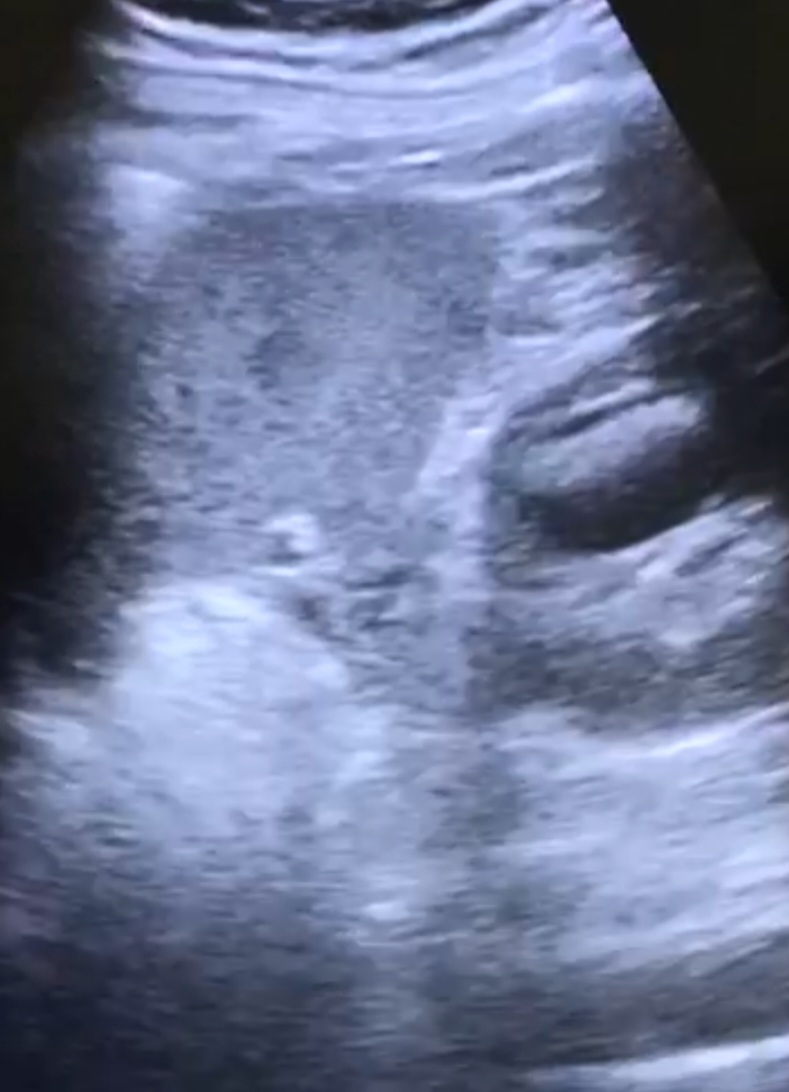

Se deriva a SUH: ID de hernia inguinal no complicada, se cita en consulta externa con cirugía; se realiza ecografía de partes blandas y se descarta la presencia de hernias. Por persistencia de síntomas acude en varias ocasiones a AP; como hallazgos casual test de aliento positivo, se pauta TTX erradicador con posterior negativización. La clínica no cedía, pese a ttx analgésico intercalado, y se acentuó en FID por lo que vuelve a consultar por su MAP y se deriva a SUH con ID de apendicitis/ hernia inguinal/orquitis; con ID de epididimitis se le pauta ATB por 7 días + urocultivo negativo. En AP se solicita cita para urología. Se le vuelve a remitir en otra ocasión desde AP a SUH: ID de dolor abdominal inespecífico y remite a su MAP. ECOABD en su MAP: imagen quística en polo superior renal izquierdo, solicita ECOABD reglada: imagen en la cara lateral del polo superior del riñón izquierdo de características quísticas de 3x2 cm, con imágenes ecogénicas en su interior con sombra acústica y con artefacto en cola de cometa (sugiere naturaleza cálcica).

Se solicita TAC para mejor valoración: Quiste en polo superior del riñón izquierdo, con leche cálcica en interior, que comunica con el sistema excretor.